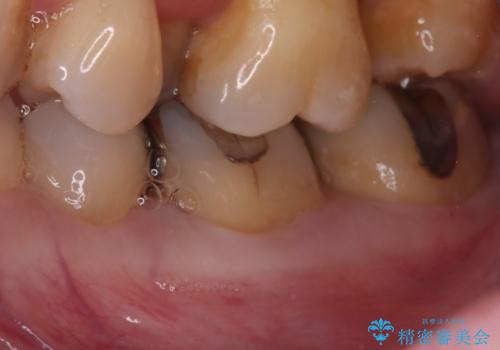

- ご友人との会話中などに、下の歯に入れてあるメタルインレーが見えてしまうのが気になり、やり変えを希望された患者様です。審美性、清掃性に優れたセラミックでの治療を希望されたため、セラミックインレー、クラウンで治療いたしました。